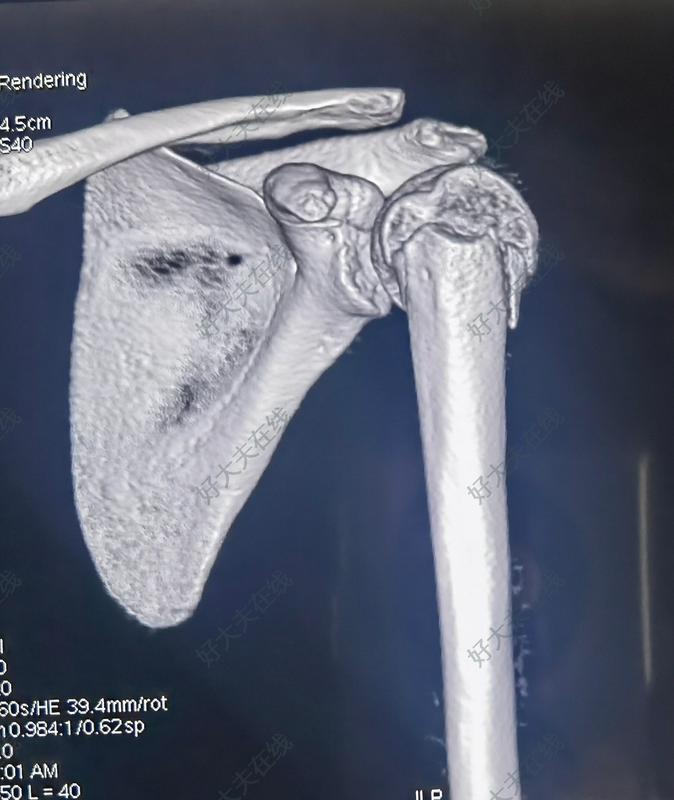

肱骨近端骨骺滑脱